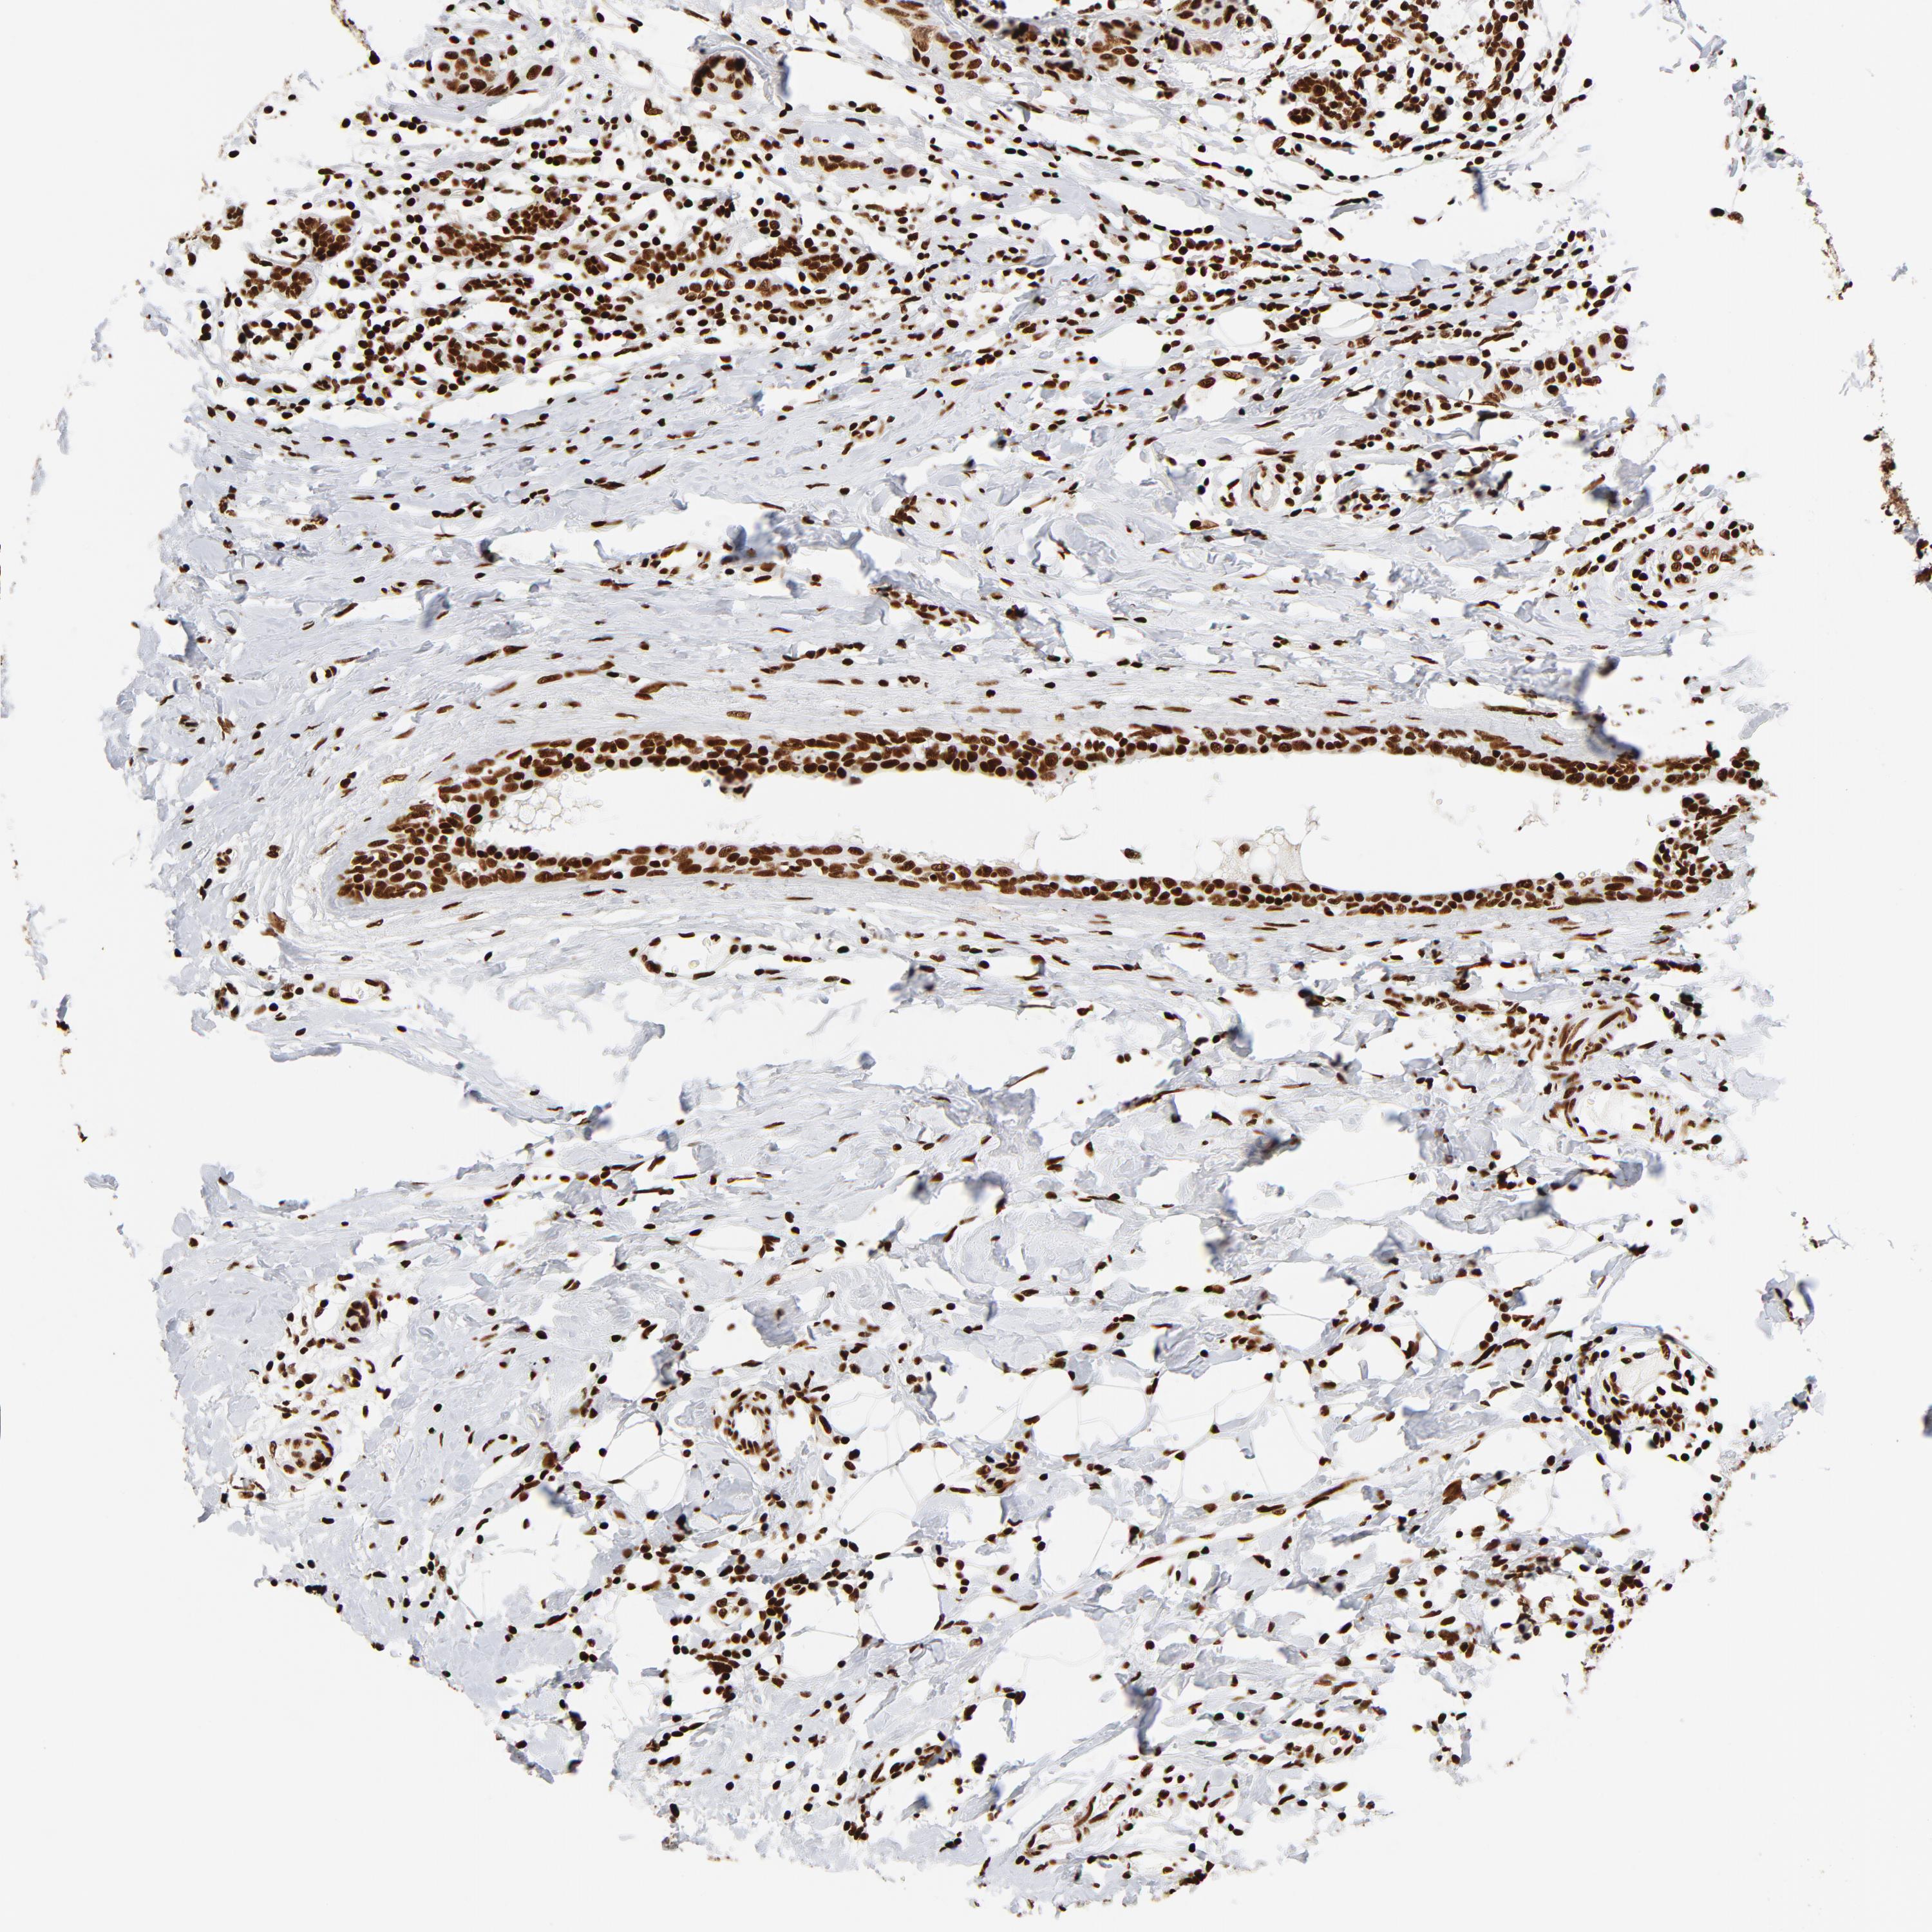

BRCA TCGA BRCA VALIDATION PROTEIN EXPRESSION